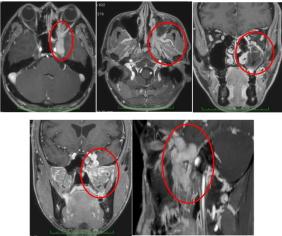

术前MRI:左侧蝶窦、筛窦、上颌窦、鼻腔、眶尖、海绵窦、左颞叶内侧、左侧鼻甲见等T1长T2信号软组织影,信号不均质,伴左侧蝶窦腔内片状短T1长T2信号,DWI示肿块弥散受限,增强后肿块明显强化,左侧视神经受压,左侧翼外肌及咽鼓管圆枕T2压脂相信号稍增高,双侧副息窦粘膜增厚,呈长T1长T2信号。双侧颈动脉鞘旁及颌下区见多发淋巴结影。

术前术后MRI对比